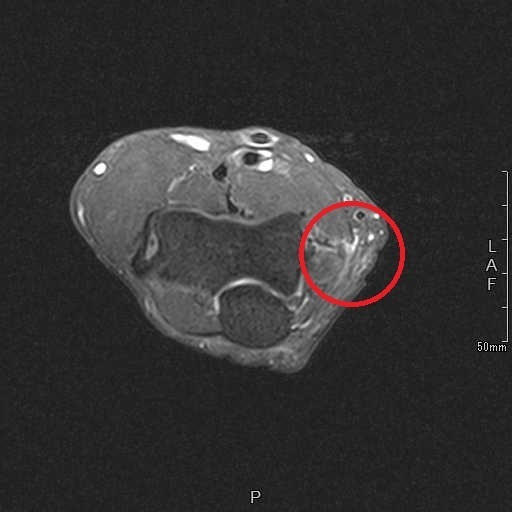

画像検査(MRI):右肘内側の屈筋群起始部の高信号(白い)

MRI画像の変化

| 治療前 1月25日 |

治療後 3月9日 |

体外衝撃波治療によって、1年半以上続いていた痛みは著明に低下し、ゴルフも問題なく行うことができるようになった。その後も症状は再発していない。